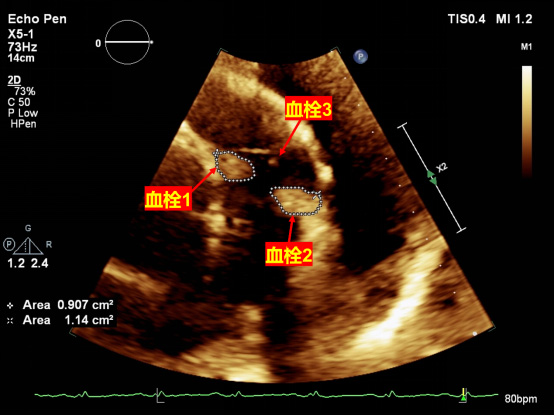

当急救车到达友谊医院时,患者已经进展为呼吸衰竭,严重缺氧,生命危在旦夕。友谊医院紧急协调,完善患者超声检查,显示右心室流出道-肺动脉内异常回声,考虑多发血栓。血管外科、麻醉科紧急于当晚21点为患者进行经皮穿刺下腔静脉滤器植入术+肺动脉造影+置管溶栓术。术后患者胸闷,腹痛症状完全缓解,低氧及呼吸衰竭纠正,5天后刘大爷顺利出院。